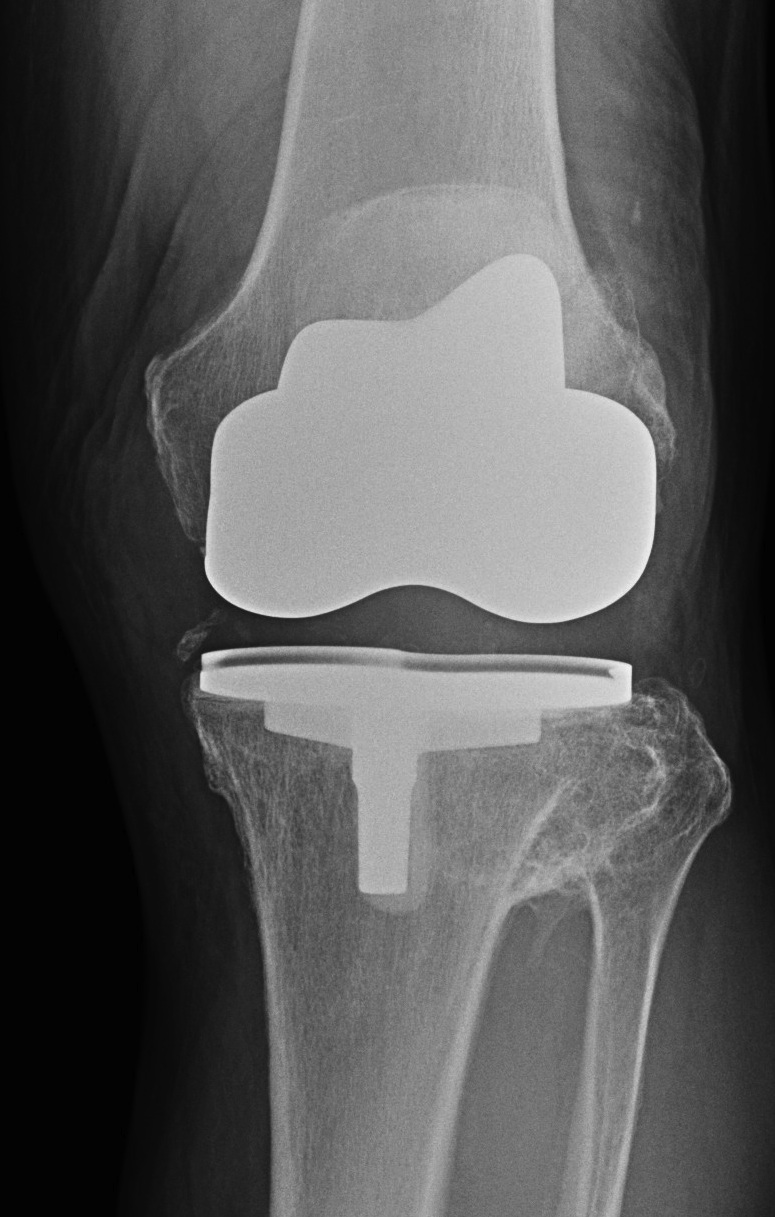

3. Offset tibial shaft medially

Seen with closing wedge

- need offset stem to avoid lateral overhang

- more common when large corrections have occurred

- have revision stems available